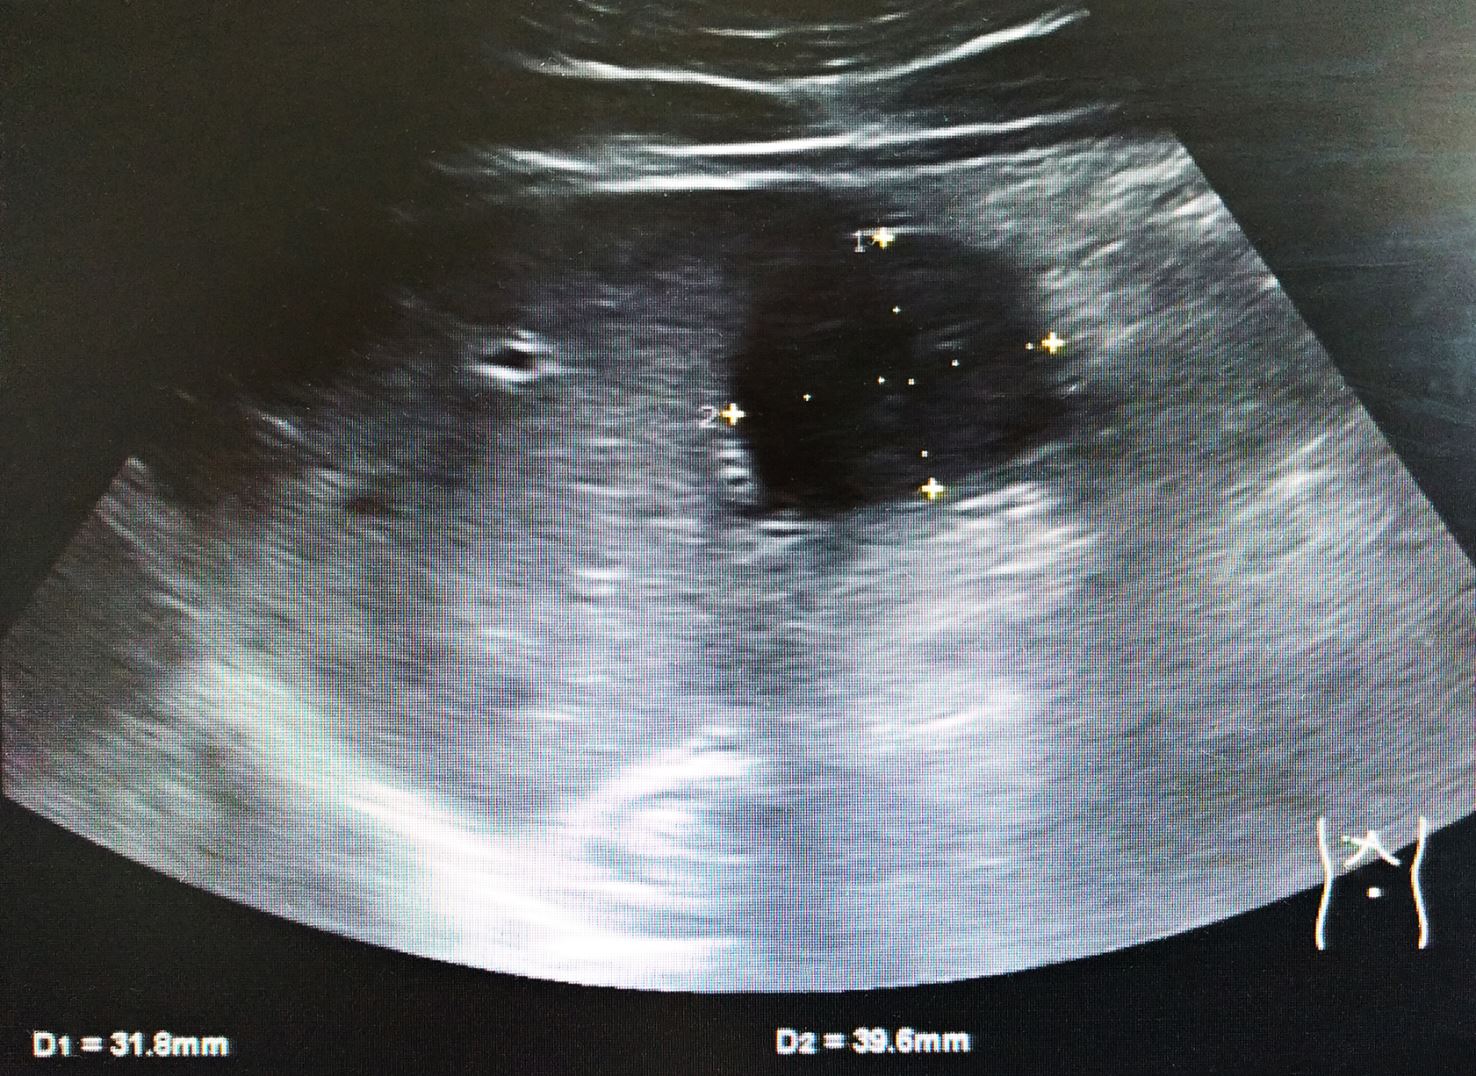

Ein 34-jähriger, 1,89 m großer und 99 kg schwerer Maler und Lackierer, der in seiner Freizeit wettkampfmäßig Volleyball spielte, stellte sich wegen akuter Oberbauchbeschwerden ohne Übelkeit, Erbrechen oder Diarrhö vor. Mit dem Ultraschallgerät kam ich der Ursache schnell auf die Spur.

Bildnachweise